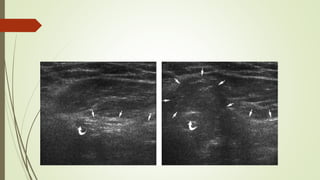

ECOGRAFÍA

 Transductor lineal 7 – 10 MHz

 Escala de grises:

 Asas intestinales con peristaltismo dentro de la hernia inguinal.

 Supino / bipedestación / Valsalva

Valsalva:

 Hernia inguinal directa: plexo pampiniforme distendido se

ve desplazado por el saco herniario.

 Hernia inguinal indirecta: ingurgitación alterada del plexo

pampiniforme.

 Doppler color:

 Demuestra la arteria epigástrica inferior y la relación con el saco

herniario.

 Hernia estrangulada.